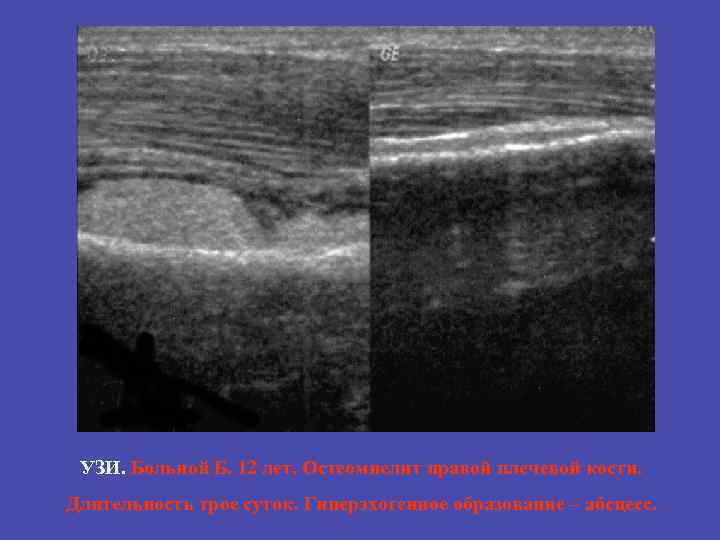

УЗИ. Больной Б. 12 лет. Остеомиелит правой плечевой кости. Длительность трое суток. Гиперэхогенное образование – абсцесс.

Отек мягких тканей визуализация надкостницы визуализация скопления гнойного субстрата между надкостницей и кортикальным слоем кости Больной Б. 12 лет. Остеомиелит правой плечевой кости. Длительность трое суток. Гиперэхогенное образование – абсцесс. 33